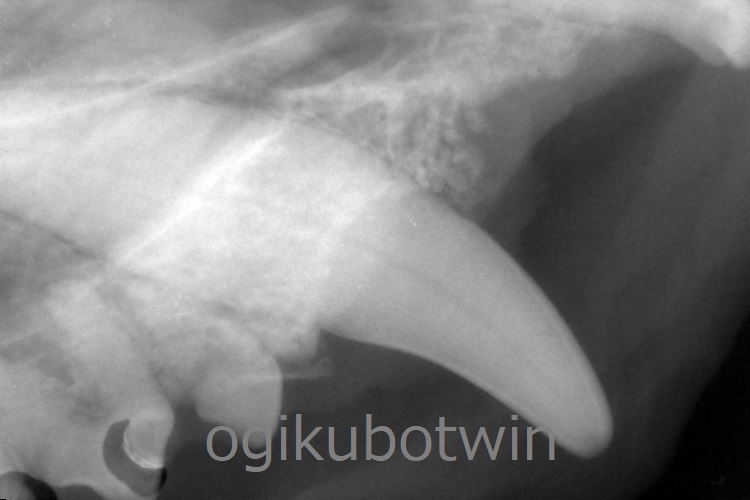

両側の上顎犬歯は歯周ポケットが深くなっていましたが、鼻腔まで到達していないことが確認できたので再生治療を行いました。

両側の犬歯ともに軟組織を除去して、骨を露出させた状態でエムドゲインとβ-TCP(骨補填剤)を用いて充填させました。

9か月後に鎮静下にてレントゲンを撮影し、再生治療の経過を確認します。

9か月後の検診時、犬歯の歯周ポケットは浅くなっており、経過良好です。